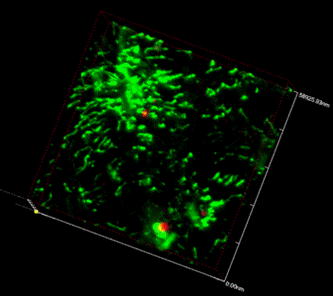

1) Depilation, wrinkled skin, hunchback and sharp decline of weight were observed in 8/13 mice. Routine blood test implicated hematopoietic reconstitution. FACS showed 86.1%±7.8% mRFP+ cells in peripheral blood of recipients. 2) mRFP+ cells were found distributing throughout the body's organs. mRFP+ Lymphocyte infiltration and inflammatory exudate were seen especially in the small intestine, lung, liver and skin (Fig.1). GFP+ cells were found surrounding mRFP+ cells in the bone marrow of the femora decalcified with semi-solid decalcification. Their interactions can be further observed clearly in bone marrow microenvironment in three-dimensional reconstruction by confocal microscope (Fig.2).

By semi-solid decalcification and three-dimensional reconstruction under confocal microscopy, the relationships of GFP and RFP marked cells in the bone marrow microenvironment are clearly demonstrated, with their original position, fluorescence and morphous. Several RFP donor's cells were found surrounded by the GFP recipient's cells, both cells cross-talking actively (200x).

By semi-solid decalcification and three-dimensional reconstruction under confocal microscopy, the relationships of GFP and RFP marked cells in the bone marrow microenvironment are clearly demonstrated, with their original position, fluorescence and morphous. Several RFP donor's cells were found surrounded by the GFP recipient's cells, both cells cross-talking actively (200x).